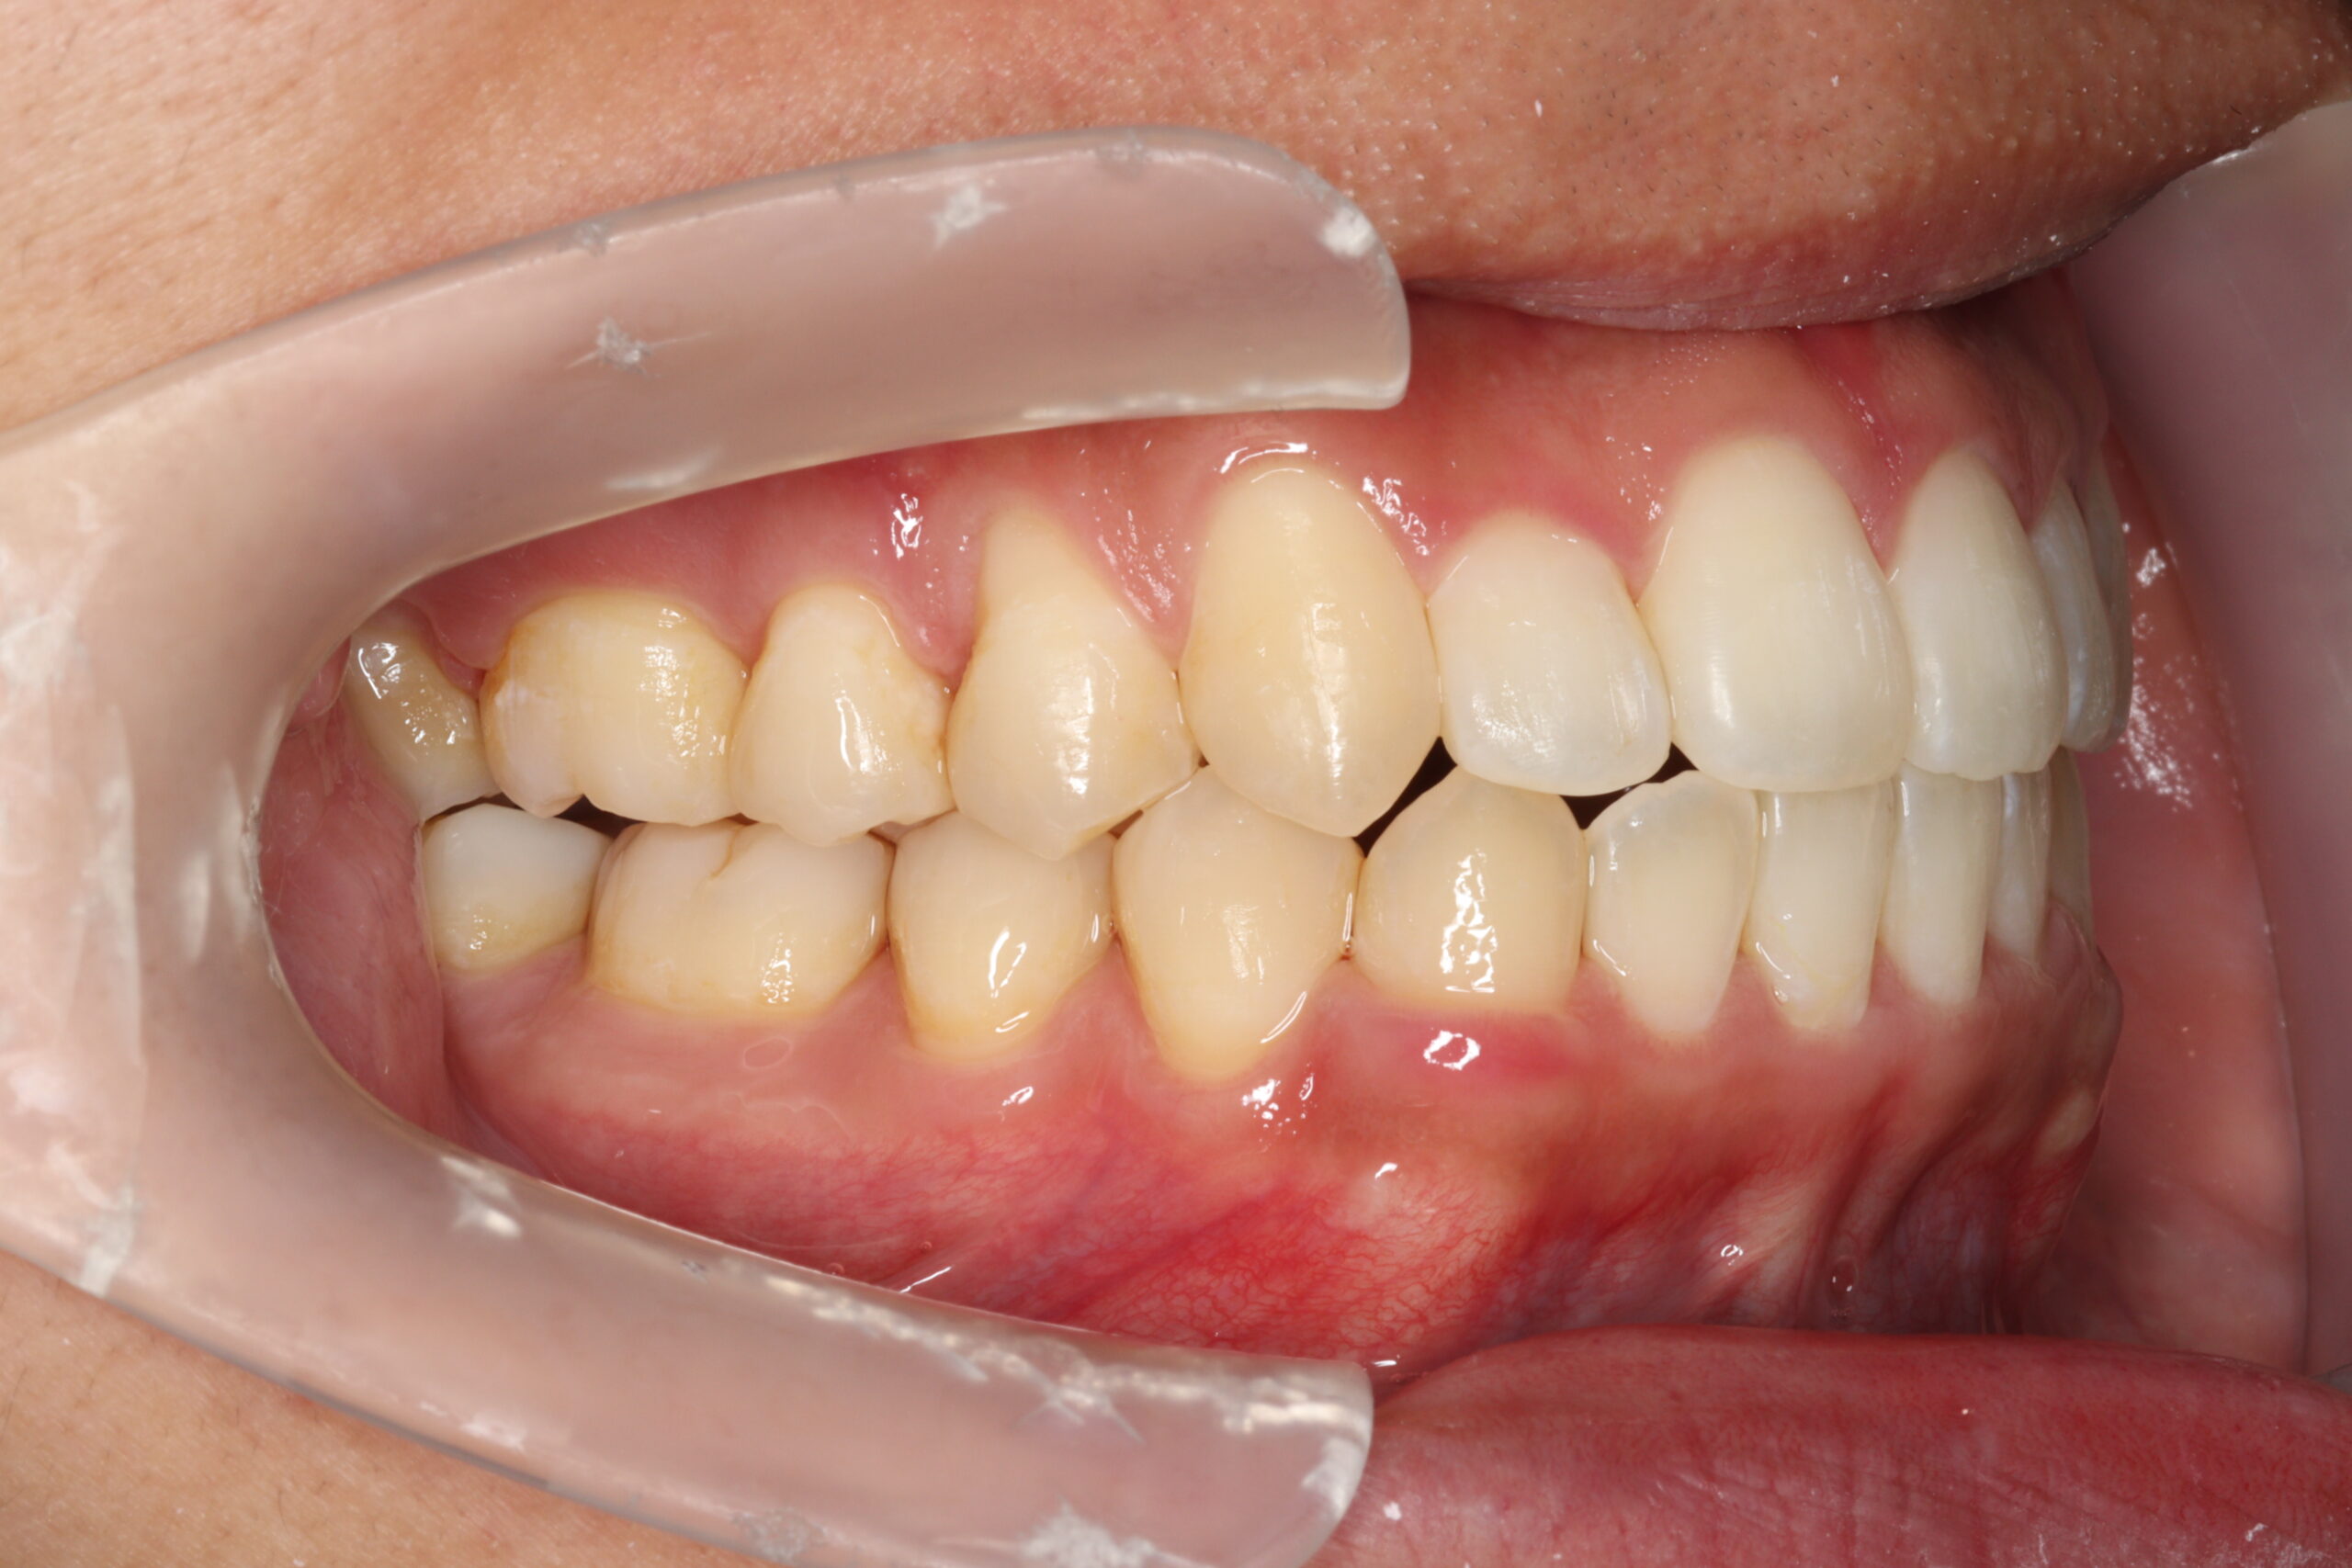

24歳男性 1年11ヵ月

24歳 男性

【主訴】でこぼこ、上下の歯が噛まない

【診断】開咬、叢生(でこぼこ)、上下顎前歯唇側傾斜、舌突出癖

【治療方法】マルチブラケット装置にて排列を行う。咬合の確立のため顎間ゴムを併用し、舌突出癖の改善のため筋機能療法を行う